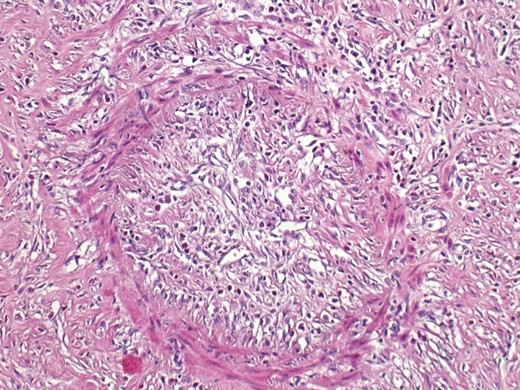

Histopathological examination showed no malignancy. In the tumorous mass, organizing granulation tissue was present. Vasculitic lesions were seen in venous structures, resembling veno-occlusive disease with signs of recanalization and with the presence of inflammatory cells, mainly lymphocytes (Fig. 3). A diagnosis of ELP was made.

Microscopic appearance with the presence of inflammatory cells, mainly lymphocytes.